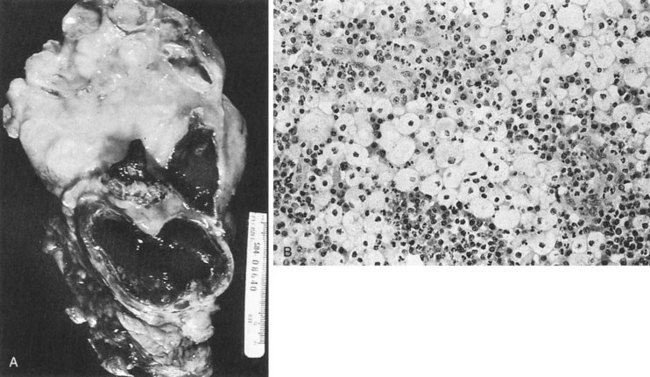

The opportunity for pathologic confirmation of acute bacterial nephritis is rare. The kidney may be edematous. Focal acute suppurative bacterial nephritis caused by hematogenous dissemination of bacteria to the renal cortex is characterized by multiple focal areas of suppuration on the surface of the kidney (Fig. 10–15). Histologic examination of the renal cortex shows focal suppurative destruction of glomeruli and tubules. Adjacent cortical structures and the medulla are not involved in the inflammatory reaction. Acute ascending pyelonephritis is characterized by linear bands of inflammation extending from the medulla to the renal capsule (Fig. 10–16). Histologic examination usually reveals a focal wedge-shaped area of acute interstitial inflammation with the apex of the wedge in the renal medulla. Polymorphonuclear leukocytes or a predominantly lymphocytic and plasma cell response are seen. Bacteria also may be present.

Figure 10–15 Acute focal suppurative bacterial nephritis. A, Surface of kidney. Arrows indicate focal areas of suppuration. B, Renal cortex showing focal suppuration destruction of glomeruli and tubules.

(From Schaeffer AJ. Urinary tract infections. In: Gillenwater JY, et al, editors. Adult and pediatric urology. Philadelphia: Lippincott Williams & Wilkins; 2002. p. 211–72.)